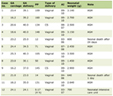

Although extrapelvic endometriosis is frequently encountered, involvement causing neurological symptoms is very rare. The clinical presentation, location and treatment of previous spinal endometriosis cases are summarized in Table 1. Symptoms are frequently due to the degree and location of the compression of neural elements from the mass, including pain, weakness, and loss of bowel and bladder control, and may even result in paraplegia. Often times, patients may experience symptoms that fluctuates with her menstrual cycle, however as the mass increases in size the symptoms may become more constant [2-8]. The symptoms may also present if the intraspinal endometriosis becomes hemorrhagic, which is most likely during the menstrual period [7, 11].

Click to view | Table 1. Diagnostic Findings in 7 Patients (Including the Present Case) Reported in the Literature, Including the Clinical Presentation, Location, Treatment and Outcome |

It has been postulated that intraspinal endometriosis probably arises via spread of endometrial tissue via Batson’s venous plexus [7]. Another hypothesis states that embryonic remains of Mullerian structures in retroperitoneum may subsequently develop into endometrial tissue after hormonal stimulation, resulting in endometriosis of retroperitoneal structures such as the spinal canal [1]. Finally, another hypothesis is that the spread of endometrial tissue may occur after surgical operations on the uterus [1, 7]. Review of the literature has shown intraspinal endometriosis to involve the intramedullary, intradural-extramedullary, and extradural compartments, including the vertebral bodies (Table 1).